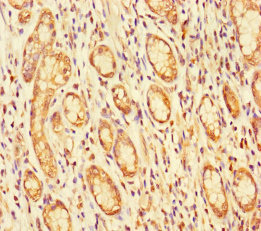

Immunohistochemistry of paraffin-embedded human gastric cancer using CSB-PA687502LA01HU at dilution of 1:100